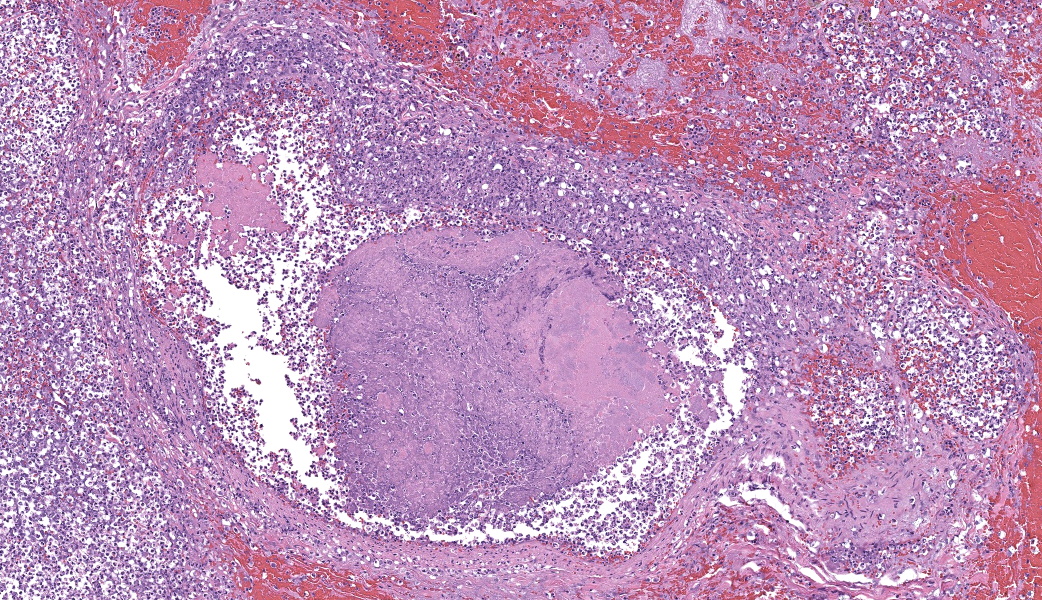

Regionally, sharply demarcated areas of the pulmonary parenchyma are markedly necrotic and replaced by abundant hemorrhage, fibrin, inflammatory infiltrates composed mainly of neutrophils and macrophages, and necrotic cellular debris. In these areas, multiple blood vessels contain thrombi consisting of large numbers of degenerate neutrophils, organizing fibrin, occasional colonies of bacterial coccobacilli, and necrotic cellular debris that variably obscure the lumen and vessel walls. Affected vessels often have smudgy, hypereosinophilic walls that are transmurally infiltrated by neutrophils, lymphocytes, and macrophages. In less affected regions, the alveolar spaces contain a small amount of fibrin, numerous foamy alveolar macrophages (some of which contain brown granular hemosiderin pigment), and fewer neutrophils and erythrocytes. There are moderate numbers of hemosiderin-laden macrophages mostly concentrated around pulmonary arteries, multifocally. Regionally, along the pleural surface there is a large amount of fibrin admixed with numerous degenerate neutrophils and necrotic cellular debris. The pleura itself is mildly thickened by fibrous connective tissue and edema and is multifocally lined by markedly reactive mesothelium, characterized by plump, rounded mesothelial cells.

Heart, right atrioventricular valve: Marked, chronic, fibrinosuppurative valvular endocarditis with intralesional bacterial colonies; Mild, multifocal, suppurative epicarditisLungs: Marked, regional, suppurative, necrotizing embolic pneumonia with vascular thrombosis and intrathrombotic bacteria; Marked, regional, fibrinosuppurative pleuritis

As the adherence of bacteria and blood components to the valve leaflets progresses, irregular, raised vegetations replace the smooth valvular surface.5 Portions of such vegetations may become detached and travel throughout the body as septic emboli.5 Emboli arising from the right side mainly affects the lungs, while emboli from the left side may dislocate and travel to distant organs, such as kidney and spleen.5

In the current case, right-sided valvular endocarditis was observed, most likely a consequence of a contaminated venous injection. Septic emboli translocated to the lungs, causing pulmonary thrombosis and infarction. Bacterial cultures of the heart and lungs revealed large numbers of E. coli and fewer Staphylococcus sp.

2. Lung: Pneumonia, embolic, necrotizing and suppurative, chronic, multifocal to coalescing, severe, with septic arterial thrombi and suppurative pleuritis.